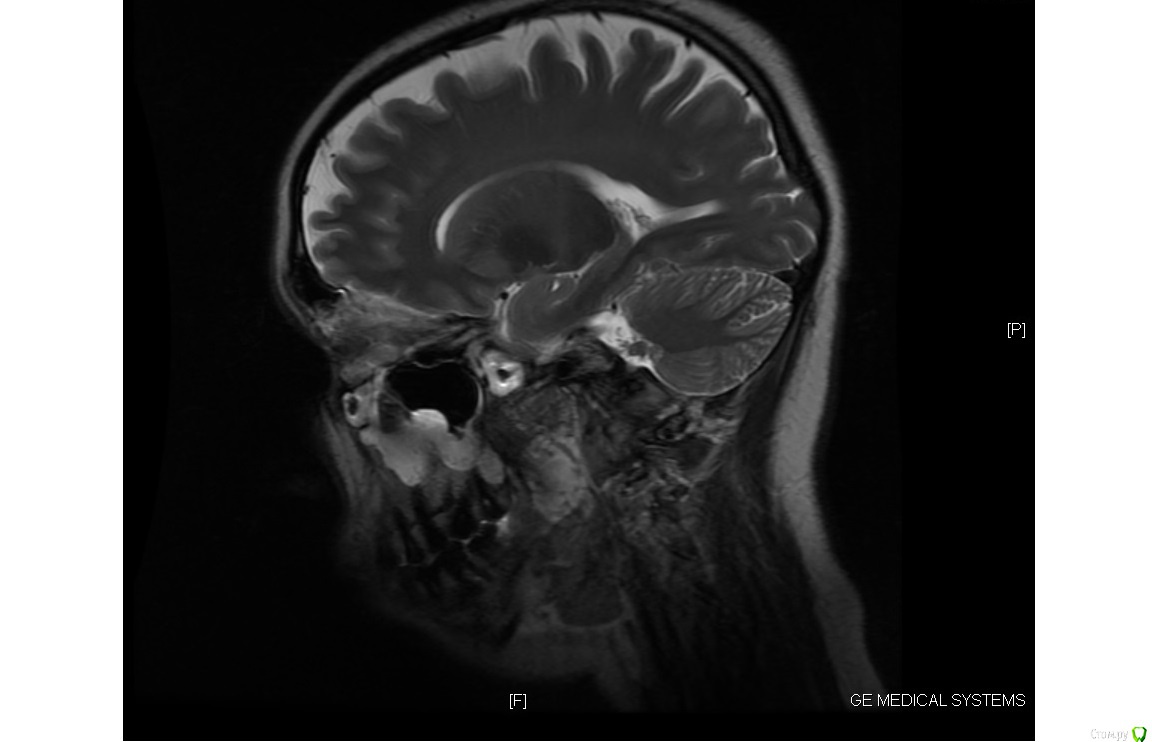

Chudo Опубликовано 14 октября, 2017 Поделиться Опубликовано 14 октября, 2017 Здравствуйте. Нужна консультация. Мне 30 лет, у меня остеопороз. 3 года после родов хожу лечить зубы как на работу (после родов состояние зубов плачевное, на панорамном снимке все видно). Сначала просто лечили кариес, удаляли нервы, ставили пломбы. У меня было две нижних 8 которые сильно сдавили мне все зубы. Мой врач все время говорила что надо ставить брекеты из-за неправильного прикуса, но денег и времени не было (маленький ребенок, отец инвалид 1 группы и муж в бесконечных командировках). В конце 2015 года я пошла удалять восьмерку, так как боль от давления на зубы стала нестерпимая. Располосовали щеку что бы поддеть 8 которая стояла горизонтально(снимок перед удалением 8 прилагаю). Зуб удаляли в Краевом клиническом стоматологическом центре Гбуз г. Краснодар. Заживало долго потому как в щеке остался осколок челюсти, месяц я ходила на перевязку и жаловалась на боль в щеке и на застрявшие нити от бинта который мне запихивали в лунку в десне, нити я вытаскивала дома сама потому что врачи их не видели, а я почему то да (никакой реакции со стороны врача не было. Я слышала только : это нормально, все пройдет). Через месяц у меня начала подниматься температура, а потом осколок из щеки стал выходить вместе с гноем из того места где мне резали щеку при удалении 8. В итоге спустя два месяца после этого удаления начался кошмар. У меня пошло воспаление по всей полости рта и верхние передние зубы начали расходиться. Все это время ходила лечила десны. Прижигала лазером воспаления в деснах, полоскала, мазала гелями, врачи все говорила что у меня просто организм подвержен постоянному воспалительному процессу и уммунитет у меня никакой . В начале 2017 дочка ударила меня затылком по нижним передним зубам, из-за чего 1 зубы стал шататься и на приему у своего зубного выяснилось, что у меня пародонтоз и что зуб у меня держится на одной только десне. Сделала мне шинирование шатающегося зуба с рекомендацией мазать гелем метрогил дента что бы десна пришла в себя и через месяц придти на прием и снять шинирование. Через месяц ситуация не улучшилась, шинирование оставили, продолжала ходить через 1-2 месяца на чистку зубов от камня и налета.В общем какая сейчас ситуация. В начале этого лета мне сказали что без брекетов я потеряю зубы, после нового снимка ортодонт сказала что брекеты она мне ставить не может из-за пародонтоза чуть ли не 3 степени и ужасного состояния моей челюсти и что зубы у меня выпадут из-за этого еще быстрее. Импланты мне сказали ставить просто некуда из-за малого количества челюстной кости. После 2 месяцев соображений ортодонт выдвинули вердикт ставить мне брекеты на мой страх и риск, если зубы выпадут, будут делать какие то протезы которые будут крепиться к боковым зубам. Ответа внятного почему мне за все это время не предлагали адекватного лечения пародонтоза я не услышала, теперь есть то, что есть ...Вот у меня к Вам дорогие специалисты 2 вопроса 1. Какова вероятность выпадения зубов при брекетах в моем случае? Я знаю что обязательно нужно вычистить все пародонтальные карманы, снять воспаление и т.д. То есть меня интересует можно ли вообще теоретически поставить брекеты с такой ушатаной челюстной костью?2. И если брекеты ставить нельзя, то что вообще делать? P.S.: Еще лет в 17 - 18 было удалено по 5 с верхней челюсти с обеих сторон из-за воспаления надкостницы (удаляли не за раз, а с интервалом в год). Рентген снимка с боку не было, есть снимок МРТ, может быть хоть чуть чуть будет что-то на них видно Ссылка на комментарий